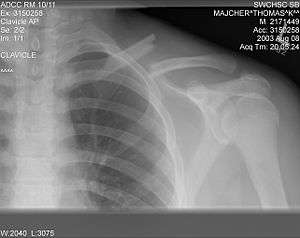

| X-ray of a left clavicle fracture | |

The basic method to check for a clavicle fracture is by an X-ray of the clavicle to determine the fracture type and extent of injury. In former times, X-rays were taken of both clavicle bones for comparison purposes. Due to the curved shape in a tilted plane X-rays are typically oriented with ~15° upwards facing tilt from the front. In more severe cases, a computerized tomography (CAT) or magnetic resonance imaging (MRI) scan is taken. However, the standard method of diagnosis through ultrasound imaging performed in the emergency room may be equally accurate in children.[1]

A discontinuity in the bone shape often results from a clavicular fracture, visible through the skin, if not treated with surgery. Surgical procedure often call for open reduction internal [plate] fixation where an anatomically shaped titanium or steel plate is affixed along the superior aspect of the bone by several screws. In some cases, the plate may be removed after healing, but this is very rarely required (based on nerve interaction or tissue aggravation), and typically considered an elective procedure. Alternatively, intramedullary fixation devices (within the medullary canal) can be implanted to support the fracture during healing. These devices are implanted within the clavicle's canal to support the bone from the inside. Typical surgical complications are infection, neurological symptoms distal the incision (sometimes to the extremity), and nonunion.